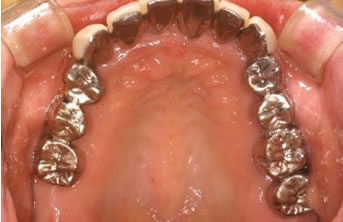

症例1

治療の特徴(患者T様)

平成13年7月7日 右下第一大臼歯頬側に膿瘍形成 著しい腫れ形成 著しい腫れ

- 男性33歳

- 平成14年11月9日 どうしても抜きたくないということで歯周外科処置する。

- その後H16から1~2カ月おきにメインテナンス。

- 平成16年6月11日 歯周治療により骨が出来てきています。

口の中から細菌を除去し、良好な環境を維持していくことによって歯周組織である歯槽骨や歯肉、歯根膜は生き生きとよみがえってきます。継続は力なりと申しますが根気良く治療を続けることで健康が回復し維持されます。

| 歯周外科に対するデメリット | 外科処置ですので麻酔が必要な処置である。全身疾患がある場合には先に体調管理を行う必要がある。処置後1週間ぐらいは治療部位のブラッシングが出来ない。冷たいものがしみることがある。 |

|---|---|

| 治療期間 | 4年7カ月 |